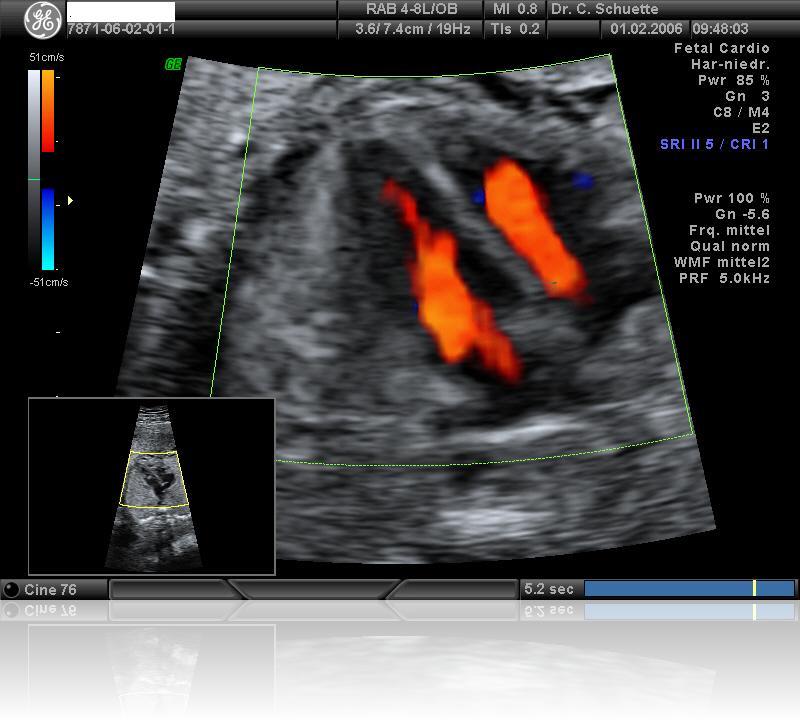

Die Untersuchung des kindlichen Herzens mit Ultraschall (fetale Echokardiographie) ist Bestandteil der weiterführenden Organdiagnostik.

Es ist heute bereits möglich, diese Spezial- untersuchung ab der 13. Schwangerschaftswoche durchzuführen und einige schwerwiegende Herzfehler können bereits dann erkannt werden.

Die endgültige Beurteilung des Herzens, seiner Funktion und der Blutflüsse erfolgt jedoch erst ab der 20. SSW und sollte in der Regel mit der 24. Woche abgeschlossen sein.

Mit Hilfe der farbkodierten Doppler-Sonographie werden weitere Details des Herzens detailliert dargestellt: